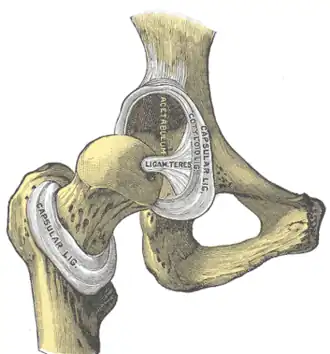

Cápsula articular

La cápsula articular es un manguito de tipo fibroso que rodea las superficies articulares. Se inserta en el hueso coxal y en la cabeza del fémur. Contribuye a darle solidez y estabilidad a la articulación.

La cápsula articular se inserta en el hueso coxal en la cara externa del rodete cotiloideo, y a nivel del fémur en la línea intertrocantérea anterior y posterior a la cabeza del fémur. Es mayor por la cara anterior que en la posterior.

Ligamentos de cadera

La cadera está dotada de 4 ligamentos principales que son fuertes bandas fibrosas que unen diferentes partes del hueso coxal con el fémur. Sirven para reforzar la articulación y evitar que se produzcan movimientos de excesiva amplitud.

- Ligamento redondo, también llamado ligamento de la cabeza del fémur, va desde la fovea capitis llamada fosita del ligamento redondo en la cabeza del fémur, hasta el fondo del acetábulo.

- Ligamento iliofemoral. También llamado ligamento de Bigelow o de Bertin, es un potente ligamento con forma de "Y" que sale de la espina ilíaca anterior inferior del hueso coxal y se inserta en la línea intertrocantérea anterior del fémur, donde se divide en dos ramas, superior (iliopretrocantérico superior o iliopretrocantereo) e inferior (iliopretrocantérico inferior o iliopretrocantíneo). El fascículo superior se encuentra reforzado, así mismo, por dos ligamentos más, el ligamento iliotendinotrocantéreo y la expansión aponeurótica del músculo glúteo menor. Es considerado el ligamento más fuerte del cuerpo humano.[1][2][3]

- Ligamento isquiofemoral: Sale del isquion, por detrás del acetábulo y se inserta en el cuello del fémur y en las proximidades del trocanter mayor.[4]

- Ligamento pubofemoral: Como su nombre indica, sale de la rama superior del pubis y se inserta, levemente por debajo del anterior, de modo que al entrecruzarse con los dos fascículos del ligamento iliofemoral dan la apariencia de una “Z” o "N". Funciona como un refuerzo de la parte inferior de la articulación.[5]